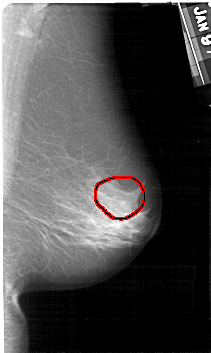

A_1378_1.RIGHT_CC

FILE: A_1378_1.RIGHT_CC.OVERLAY

TOTAL_ABNORMALITIES 1

ABNORMALITY 1

LESION_TYPE CALCIFICATION TYPE PLEOMORPHIC DISTRIBUTION SEGMENTAL

ASSESSMENT 4

SUBTLETY 2

PATHOLOGY BENIGN

TOTAL_OUTLINES 1

BOUNDARY